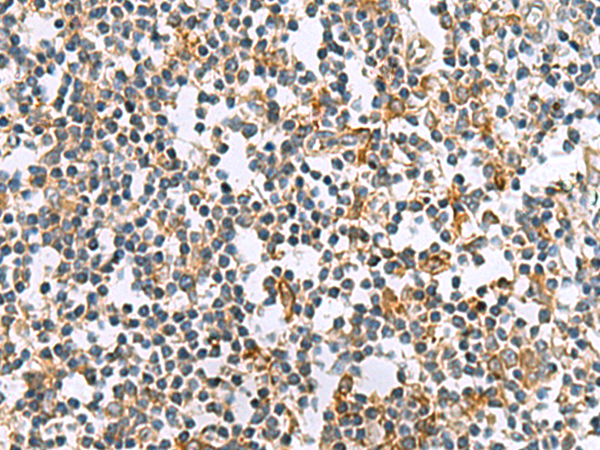

分类: 科研抗体货号: P10296别名:应用: IHC反应种属: Human, Mouse